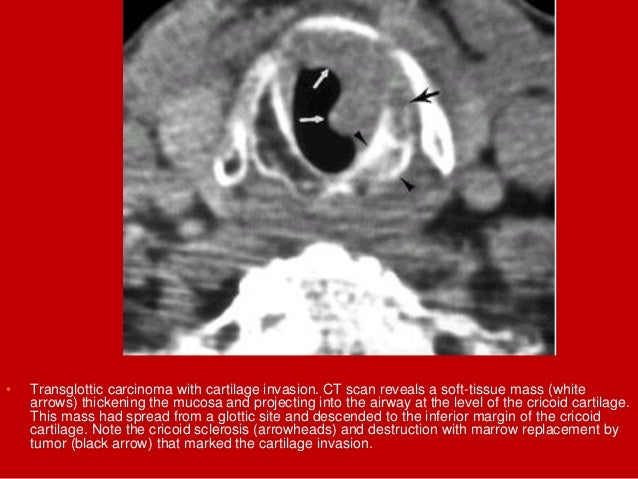

40. 40. • Transglottic carcinoma with cartilage invasion. CT scan reveals a soft-tissue mass (white arrows) thickening the mucosa and projecting into the airway at the level of the cricoid cartilage. This mass had spread from a glottic site and descended to the inferior margin of the cricoid cartilage. Note the cricoid sclerosis (arrowheads) and destruction with marrow replacement by tumor (black arrow) that marked the cartilage invasion.